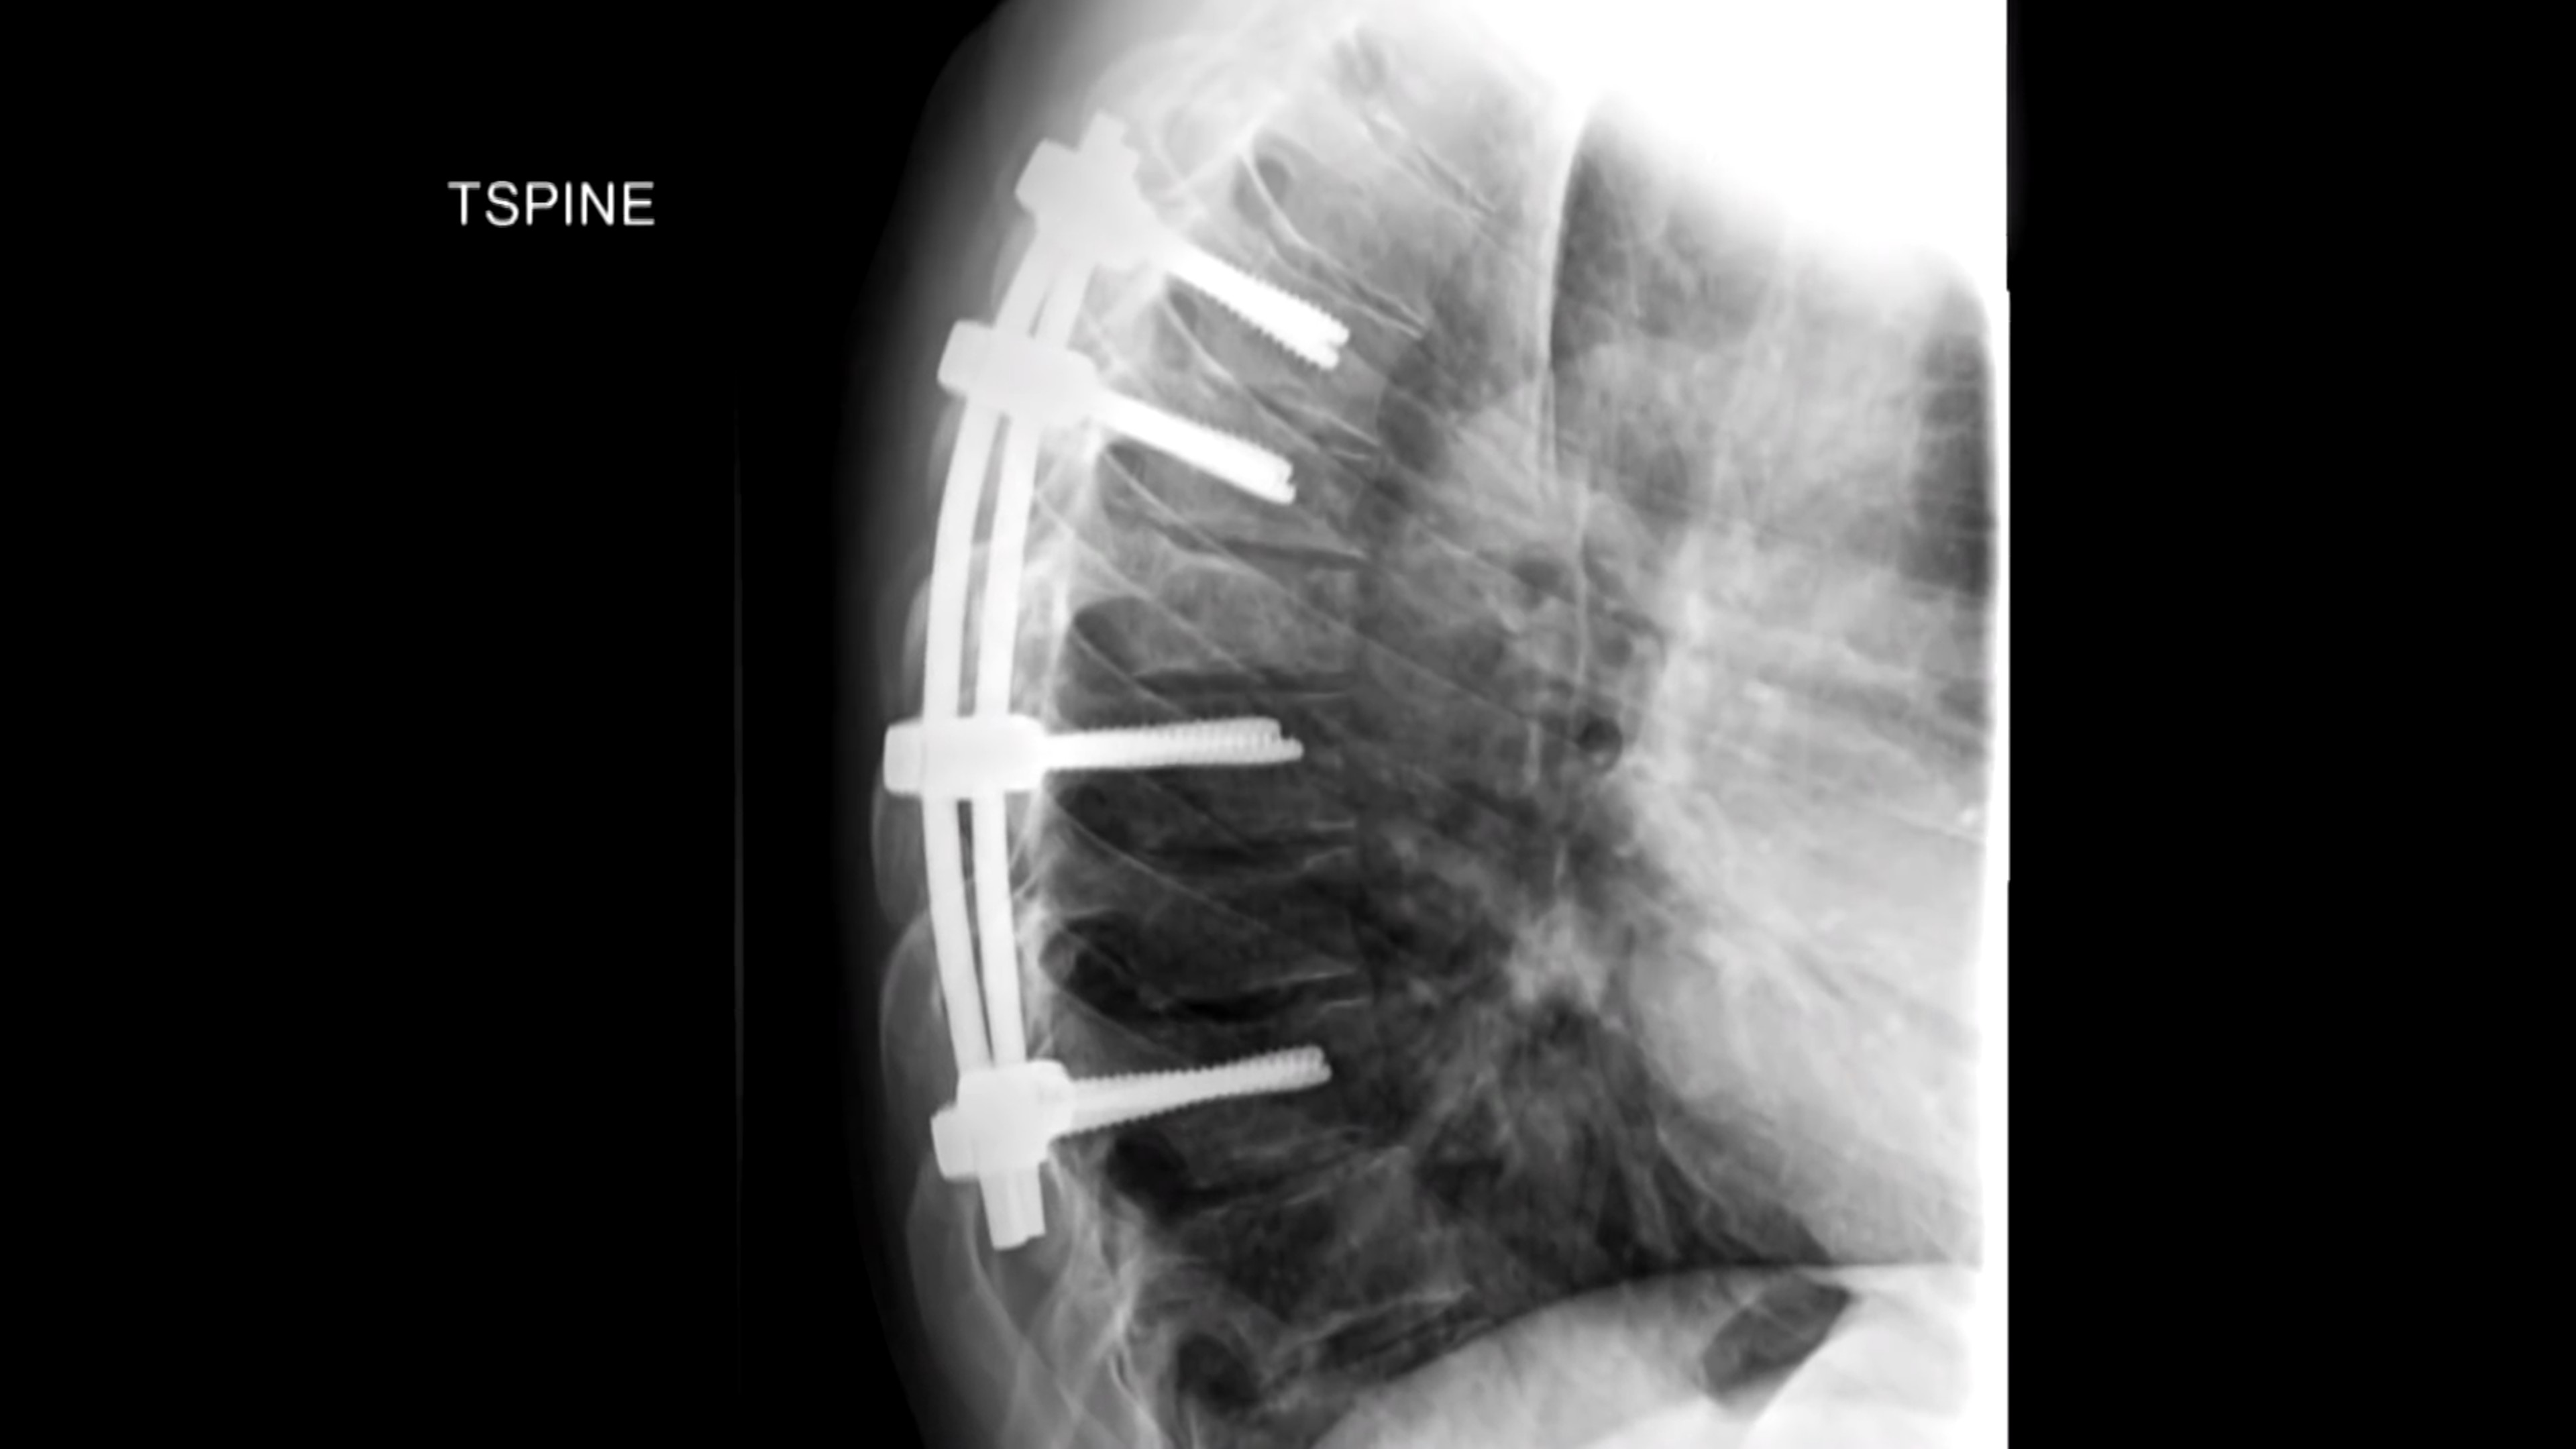

事故造成它肺部穿孔,脊骨椎骨骨折。

事故造成他十多处骨折,

背部也被打入了钢钉。